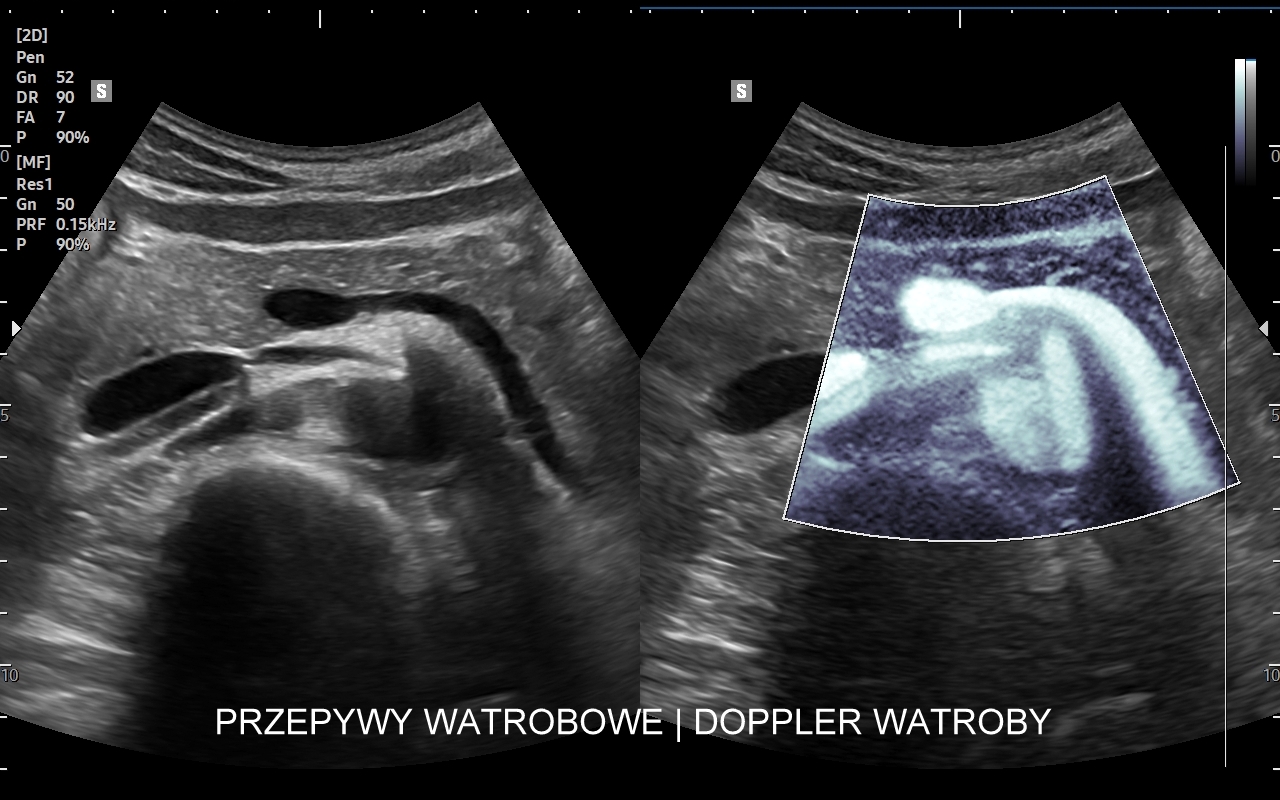

Ocena USG wątroby po przeszczepie, w tym Doppler przepływy wątrobowe, wykonywana jest zarówno w bezpośrednim szpitalnym okresie po zabiegu transplantacji, jak i w trakcie regularnej oceny ambulatoryjnej. W ramach badania sprawdzane są cechy ewentualnego odrzucania przeszczepu lub jego zapalenia, prawidłowość unaczynienia wątroby, szczelność połączeń tętniczych, żylnych oraz dróg żółciowych, a także ewentualne oznaki zwężenia lub niedrożności tychże połączeń. Interdyscyplinarna Pracownia USG prowadzona od 2011 r. przez dr Tomasza Szczepańskiego, pierwotnie w Opiece Medycznej Golden Care, jest jedną z niewielu instytucji we Wrocławiu i na Dolnym Śląsku wykonujących ocenę pacjentów po przeszczepach wątroby.